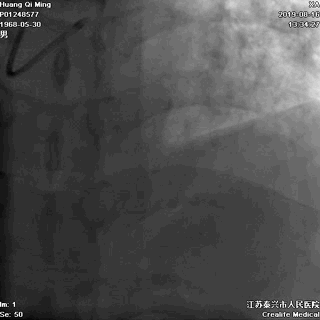

冠状动脉造影

右冠状动脉无严重狭窄

左主干前分叉处血管正常

LCX近中段病变,狭窄最重达90%

LAD中远段血管偏细,弥漫性病变,狭窄达90%